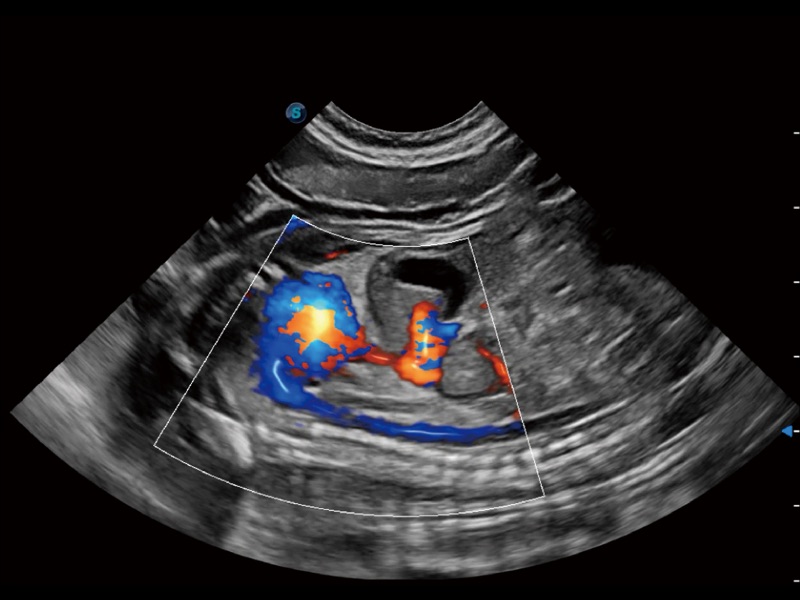

通过创新的 Matrix E自适应滤波器和超长时间域算法,极大提升超低速微细血流的检出能力,同时更精准地滤除软组织和噪声信号,为兽用医生提供以往无法通过常规血流获得的疾病诊断信息。

通过色彩血流和实时宽景相结合,可观察到完整的静脉或动脉的血流,方便医生检查。实时扫查过程中,如有任何操作失误也可以很容易地进行回扫擦除,而不会中断扫查。

采用红、橙、黄、绿、青、蓝、紫这七种肉眼最为敏感的色彩,直观地显示组织内血流灌注的时间先后信息,更精准捕捉血流灌注走行细节。